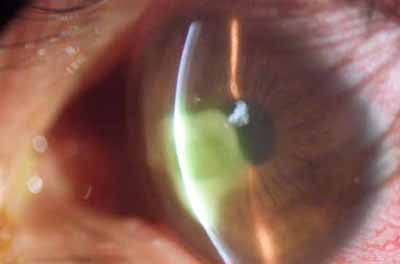

Perineuritis

No tienen los bulbos terminales de las dendritas del Herpes Simple

Formación de lineas epiteliales elevadas que pueden dar la imagen de Seudodendrítas

Formación de lineas epiteliales elevadas que pueden dar la imagen de Seudodendrítas

Formación de lineas epiteliales elevadas que pueden dar la imagen de Seudodendrítas + Perineuritis